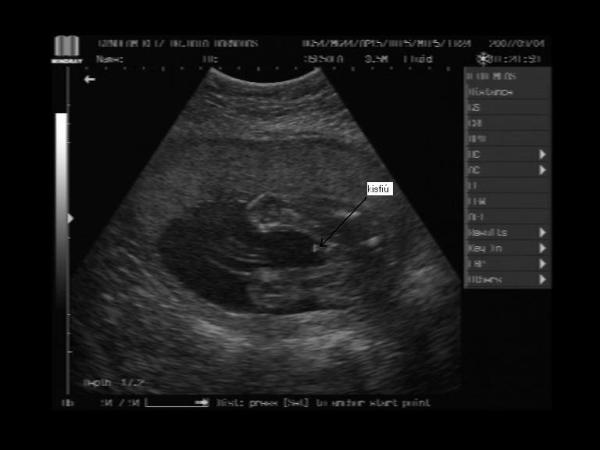

És a bébi 24 hetesen:

Kép A kis pöcsös